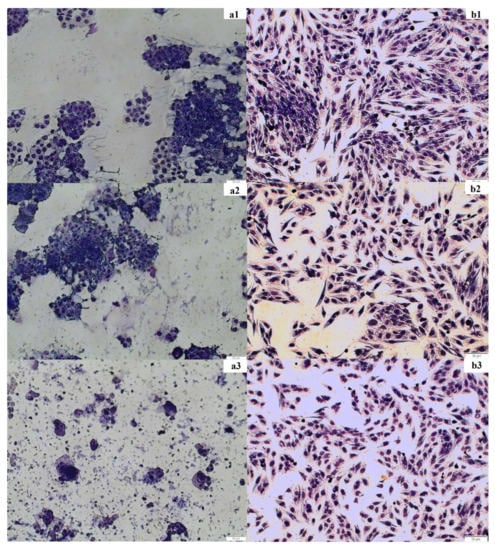

2.2.3. May–Grünwald–Giemsa Staining

4.8. May-Grünwald-Giemsa Staining